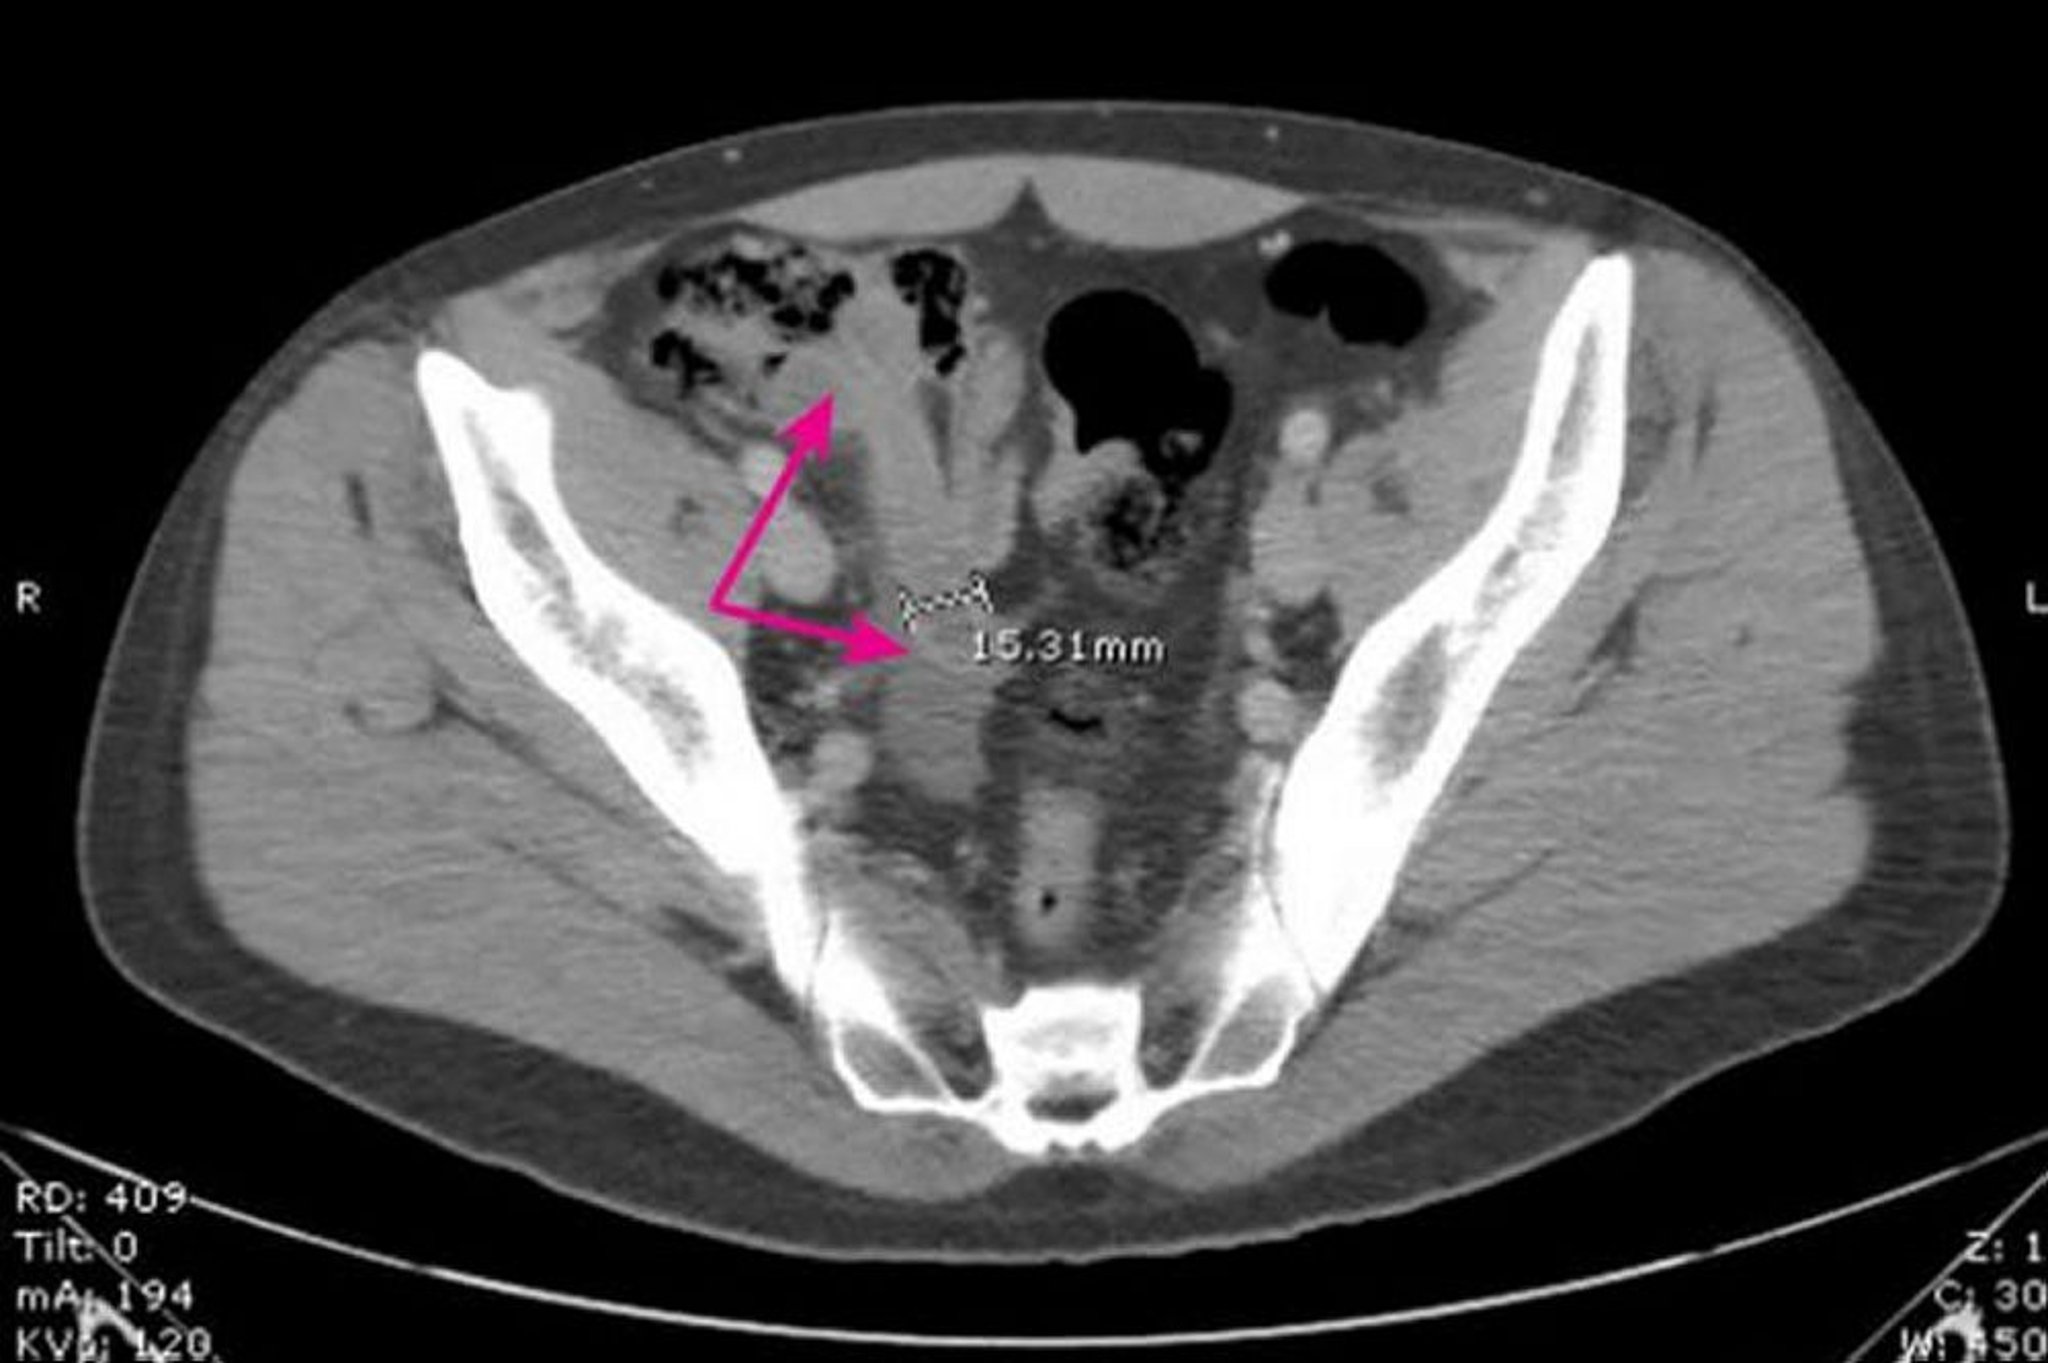

Appendicite aiguë

Cette image montre un appendice dilaté, à paroi épaissie (flèches) mesurant 15,31 mm de diamètre avec des modifications inflammatoires environnantes.

Image provided by Parswa Ansari, MD.